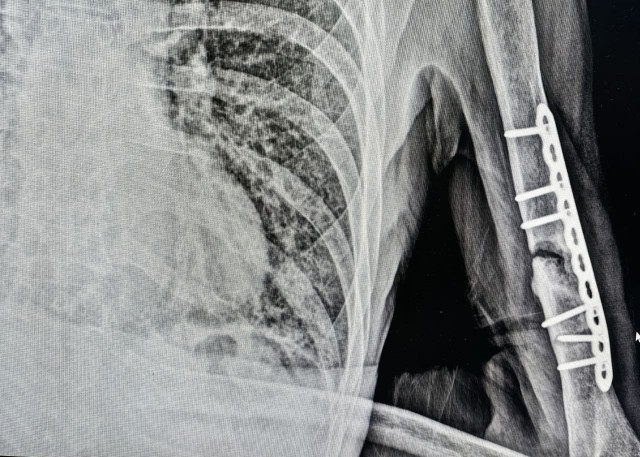

В 2020 году мужчина попал в ДТП и получил перелом плеча. За это время он перенес две операции, но кость так и не срослась. Ситуация казалась безвыходной, но ему помогли врачи Сургутской травмбольницы. Они приняли решение соединить 70-летнему пациенту кость с помощью сложной операции – реостеосинтеза с костной пластикой.

– Для операции взяли кусочек малоберцовой кости в качестве трансплантата. Чтобы не травмировать донорскую зону, сделали аккуратный продольный разрез. Трансплантат вставили в внутреннюю часть плечевой кости, чтобы поддержать и соединить сломанные части. Потом все закрепили накостной пластиной, чтобы кость хорошо срослась, – говорится в сообщении.

ФОТО Сургутской травмбольницы